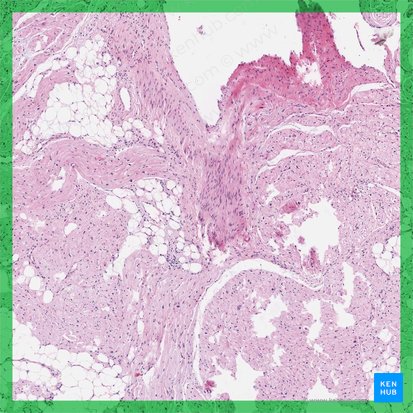

The sinuatrial node is found in the posterolateral wall of the sinus of venae cavae in the right atrium (hence ‘sinu-’ + atrial) close to the junction of the superior vena cava with the right atrium, deep to the crista terminalis. It is made up of specialized cardiomyocytes, also known as nodal cardiac muscle cells or ‘pacemaker’ cells which are grouped together into an elongated ellipsoid bundle with a length of 8 to 25 mm. Nodal cardiac muscle cells are smaller than typical cardiomyocytes and lack intercalated discs. They are capable of self-excitation, meaning they are able to independently produce spontaneous electrical impulses. They communicate directly with and excite adjacent/perinodal cardiomyocytes through gap junctions and thus induce the contractions of the heart.